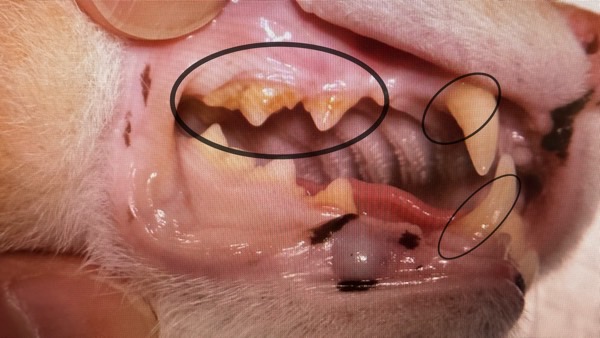

歯肉炎はなし、歯垢の蓄積も軽度で、奥歯の歯垢除去だけで済みました。

[ 処置前 ]右側

[ 処置前 ]左側

[ 処置後 ]右側

[ 処置後 ]左側

もともと大きなトラブルもなく、正直「5万円分の価値があったのか…?」と複雑な気持ちもありました。

ですが、もし歯茎に炎症があったら薬を飲ませることになったり、状態が悪ければ、歯を削ったり抜いたりした可能性もあったとのこと。